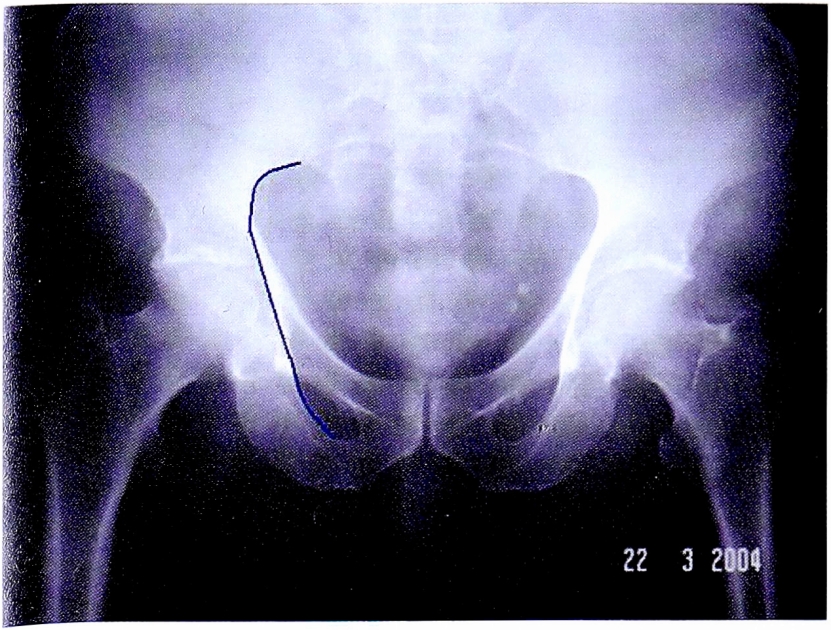

На прямой обзорной рентгенограмме (рис. 30) сохранена непрерывность подвздошно-седалищной линии. Исходя из этого, можно исключить все типы переломов, при которых имеется повреждение задней колонны, а также обеих колонн вертлужной впадины. С клинической точки зрения на этом этапе экспресс-диагностики из возможных 10 вариантов переломов вертлужной впадины остается 3 вероятных повреждения.

Рис. 30. Первый этап определения перелома передней колонны.

Fig. 30. First step of anterior column fracture diagnostic.

Целостность контуров заднего края позволяет исключить перелом задней стенки (рис. 31) — остается 2 возможных варианта.

Рис. 31. Третий этап определения перелома передней колонны.

Fig. 31. Third step of anterior column fracture diagnostic.

Сочетание повреждений подвздошно-гребешковой линии и контуров запирательного отверстия позволяет уточнить окончательный диагноз: перелом передней колонны вертлужной впадины (см. рис. 31).